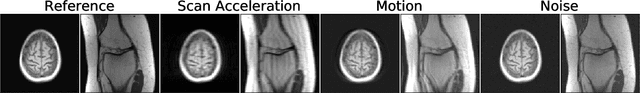

Abstract:Image quality assessment (IQA) algorithms aim to reproduce the human's perception of the image quality. The growing popularity of image enhancement, generation, and recovery models instigated the development of many methods to assess their performance. However, most IQA solutions are designed to predict image quality in the general domain, with the applicability to specific areas, such as medical imaging, remaining questionable. Moreover, the selection of these IQA metrics for a specific task typically involves intentionally induced distortions, such as manually added noise or artificial blurring; yet, the chosen metrics are then used to judge the output of real-life computer vision models. In this work, we aspire to fill these gaps by carrying out the most extensive IQA evaluation study for Magnetic Resonance Imaging (MRI) to date (14,700 subjective scores). We use outputs of neural network models trained to solve problems relevant to MRI, including image reconstruction in the scan acceleration, motion correction, and denoising. Seven trained radiologists assess these distorted images, with their verdicts then correlated with 35 different image quality metrics (full-reference, no-reference, and distribution-based metrics considered). Our emphasis is on reflecting the radiologist's perception of the reconstructed images, gauging the most diagnostically influential criteria for the quality of MRI scans: signal-to-noise ratio, contrast-to-noise ratio, and the presence of artifacts.